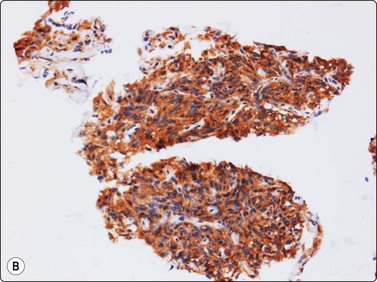

Smears from synovial sarcoma are usually highly cellular (Fig. 15.57A). The typical appearance is a mixture of tissue fragments and dispersed cells. Mitotic figures can be found in almost every case, especially in the tissue fragments. Bare nuclei are common. A hemangiopericytoma-like vascular pattern with branching capillaries (’staghorn’ pattern) is commonly seen in fragments. The cells are small to medium in size. Nuclei are rounded or ovoid with finely granular, bland chromatin and nucleoli are small and inconspicuous. Intact cells have thin uni- or bipolar cytoplasm. Vaguely acinar-like structures may be seen in the periphery of fragments (Fig. 15.57B). Mast cells are prominent in some cases. A myxoid background matrix has been reported in some cases.74 An obvious biphasic pattern is only infrequently seen in our experience. The cytology of mono- and biphasic synovial sarcoma has been reported in two large series.75,76 The cytomorphology of the poorly differentiated variant77 (involving the entire tumor or focally in other subtypes) is relatively unknown and has been described in few cases (Fig. 15.58).78-80 Poorly differentiated fibrosarcoma-like synovial sarcoma is extremely difficult to distinguish from MPNST and the rare fibrosarcoma. A reliable cytologic diagnosis of synovial sarcoma is important since neoadjuvant therapy is commonly applied before surgery. Even if synovial sarcoma is strongly suspected in an FNB smear, adjunctive diagnostic methods are almost always necessary to reach a confident diagnosis. The majority of synovial sarcomas stain positively for EMA and keratins 7 and 19 (although often focally); positive staining for CD99 and bcl-2 has also been reported. Cytogenetic analysis is a most important valuable adjunct. FISH (Fig. 15.59) and RT-PCR of aspirated material used for detection of the two most common gene fusion products (SYT/SSX1 and SYT/SSX2, respectively) is more effective than chromosomal analysis of cytologic material to diagnose the translocation t(X;18)(p11;q12).81

image image

Fig. 15.57 Synovial sarcoma

(A) Smears are usually highly cellular; the typical appearance is a mixture of tissue fragments and dispersed cells (H&E, LP); (B) Vaguely acinar-like structures may be seen in the periphery of fragments (MGG, HP).